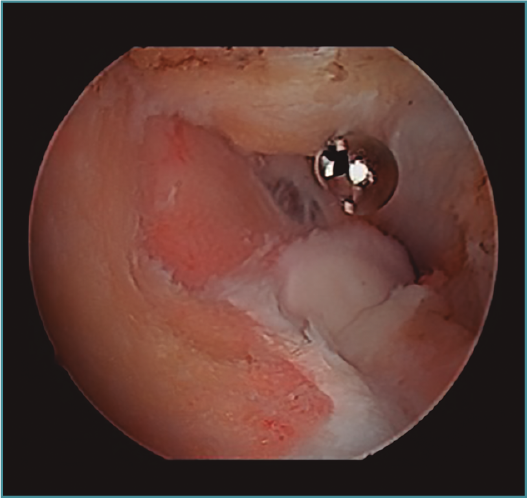

Acto seguido, realizamos nuestra secuencia de trabajo descrita anteriormente (visualización, creación de espacio, trabajo óseo y trabajo de partes blandas). El fresado óseo debe realizarse siempre con el instrumental motorizado orientado hacia el húmero, para evitar las lesiones de partes blandas. El uso de fresas o el sinoviotomo en modo no oscilante y a alta velocidad nos permitirá eliminar los osteofitos que interfieran con la movilidad, especialmente aquellos que ocupan la fosa radial o coronoidea (Figura 8). También es frecuente tener que eliminar osteofitos que aumentan la altura de la coronoides (Figura 9). Una vez eliminado el material óseo (Figura 10), flexionamos el codo para comprobar el aumento de flexión conseguido, que no será completo hasta que liberemos la cápsula posterior y la banda posterior del ligamento colateral medial. Como último paso en la cámara anterior, procedemos a la eliminación de la cápsula articular. Introducimos un Basket recto desde el portal anteromedial y vamos mordiendo la cápsula, atrapándola, cortándola y realizando un movimiento de batido hacia proximal para separar el fragmento capsular de las partes blandas anteriores. Progresamos lateralmente, descubriendo el vientre muscular del braquial anterior, hasta que aparezca tejido graso detrás de la cápsula resecada. En este momento, cambiamos los portales y miramos desde el portal anteromedial proximal y utilizamos la pinza Basket desde el portal anterolateral. Una vez realizada esta capsulotomía amplia, usamos el sinoviotomo para eliminar los restos capsulares proximales. Durante todo este proceso, utilizamos un retractor desde el portal anterolateral proximal para tensar la cápsula y proteger, sobre todo, el nervio radial, que queda situado justo en la grasa lateral al músculo braquial y anterior a la cabeza del radio, y a escasos milímetros de nuestro instrumental de trabajo; aunque no es aconsejable, es posible traccionar de él e introducirlo en la articulación con ayuda de un palpador introducido en la grasa que lo recubre. El nervio mediano se encuentra medial al músculo braquial, pero en un plano bastante más anterior, lo cual hace que esté mucho más protegido(12,13).

Figura 8. Osteofitos ocupando la fosa radial y coronoidea, observados desde el portal anteromedial proximal.